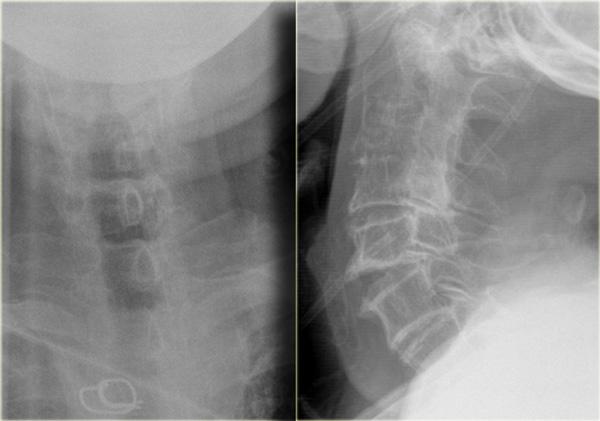

Hình bên trái là hình ảnh của một hành khách không thắt dây an toàn, bị văng ra khỏi xe và được phát hiện trong tình trạng lú lẫn và kích động tại hiện trường.

Bệnh nhân được đặt nội khí quản và chuyển đến bệnh viện, tại đây được xác định bị liệt tứ chi.

Trên hình định vị (scout view), có thể thấy mối quan hệ bất thường giữa hộp sọ và cột sống cổ.

Hình CT cắt ngang cho thấy máu bao quanh thân não.

Trên các hình ảnh bên trái, lưu ý mối quan hệ bất thường giữa basion, opisthion, đỉnh mỏm răng và cung sau đốt đội.

Khoang dưới nhện tăng tỷ trọng do xuất huyết (mũi tên).